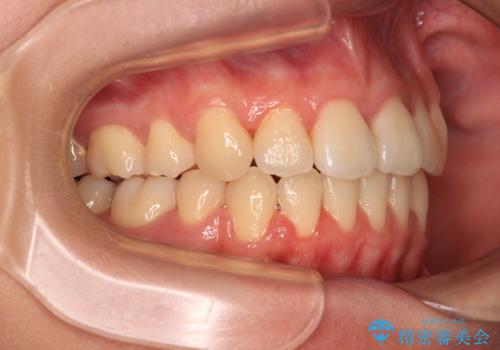

- 抜歯矯正の後戻りを気にして来院された患者様です。

舌の突出癖によるオープンバイトになっていたため、インビザラインによるマウスピース矯正をおすすめしましたが、自己管理の自信がないとのことで、ワイヤー装置による矯正治療を行うこととしました。

舌の突出癖が認められると、上下前歯の隙間を閉じることができません。

舌のトレーニングをしっかりと行っていただくことで、歯列を整えることができます。